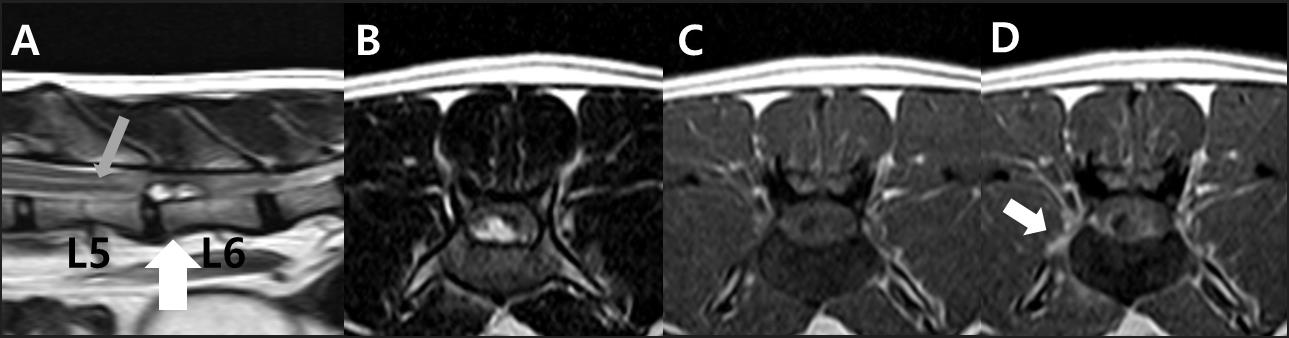

고양이 척수 경막외 섬유성 수막종의 MRI 단면

이번 연구는 고양이에서 발생한 척수 경막외 수막종(Spinal Extradural Meningioma) 사례를 통해, 요추 디스크 질환으로 오인될 수 있는 척수 종양의 감별 진단 과정과 임상적 의미를 다룬 증례 보고(case report)입니다.

척수 경막외 수막종은 임상 증상이 디스크 질환과 유사하게 나타날 수 있어 정확한 영상 진단과 임상적 판단이 매우 중요한 질환입니다.